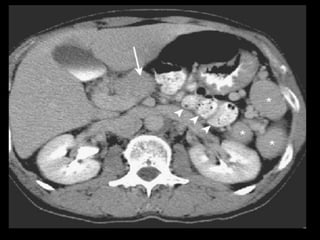

Pâncreas anular

A CPER mostra um ducto pancreático aberrante

circundando o duodeno.

O local de drenagem desse ducto é variável;

A RM e a TCMD mostram tecido pancreático

circundando o duodeno, que conserva a densidade

e a intensidade de sinal do pâncreas normal

remanescente, tanto no exame basal como após a

administração de contraste.

Imagens T1 com supressão de gordura são úteis.

Diferenciação com neo pancreática ou duodenal.

T1: tecido pancreático ao redor da segunda porção